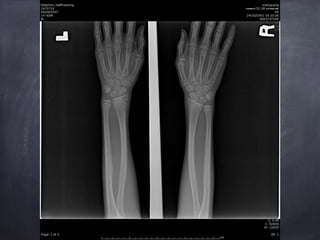

ผู้ป่วยชายไทย อายุ 14 ปี

Chief complaint : ปวดข้อมือซ้าย 30 นาที

E : tender Lt. wrist, mild swelling, limit ROM due to pain, NV intact

Extremities : tender at Lt. radial styloid, mild

swelling, limit ROM due to pain, NV intact

Tender at Lt. radial styloid R/O fracture

Epiphyseal plate injury Salter harris type 2 Lt.

distal end redius